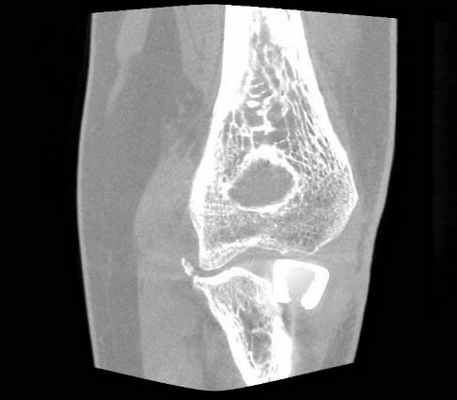

3. Непоправимые переломы: установка эндопротеза

Осложнения протеза лучевой кости, закрепленного снаружи: лучевая кость с протезом оказалась длиннее, чем была раньше. © Gelenk Klinik

При многооскольчатых переломах головки лучевой кости ее реконструкция невозможна. В таком случае стоит задумать об имплантации протеза.

С медицинской точки зрения данное вмешательство является довольно сложным. Диаметр протеза должен соответствовать изначальному размеру головки лучевой кости. Также протез не должен заметно выступать по отношению к области сустава. Такой феномен называется “Overstuffing” и его следует избегать во что бы то не стало. Только так пациент сможет избежать болей, сопровождающихся ограниченной подвижностью и усиленного износа суставного хряща в локте.